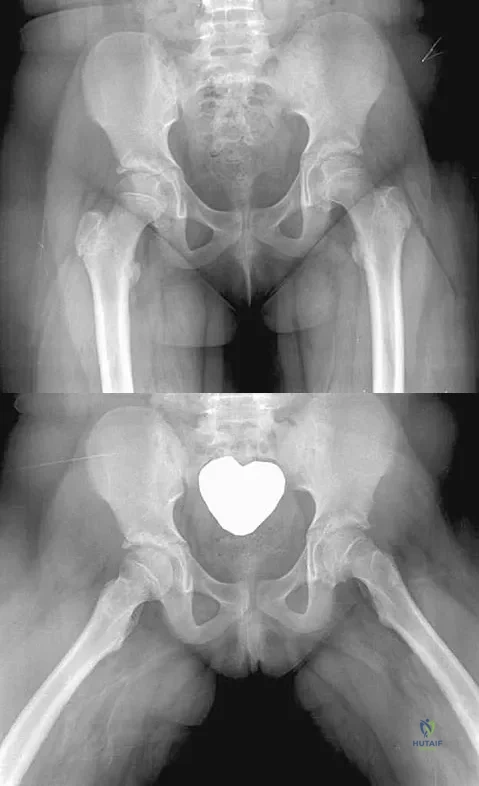

An obese 10-year-old boy has had left groin pain and a limp for the past 2 months. Examination reveals decreased abduction and internal rotation. Laboratory studies show normal renal function and an elevated thyroid-stimulating hormone (TSH) level. AP and frog lateral radiographs of the pelvis are shown in Figures 30a and 30b. What is the best course of action?

Detailed Explanation